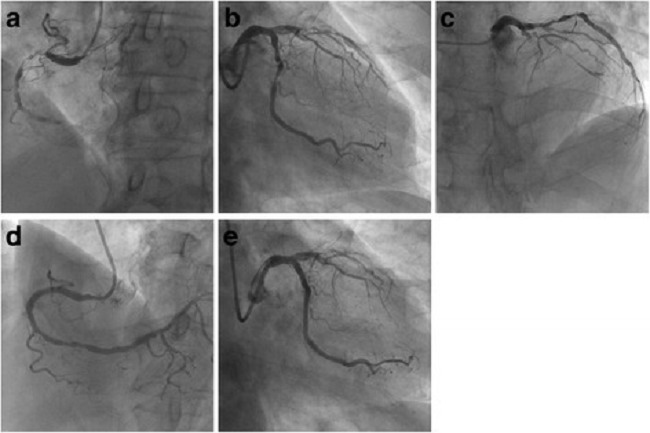

Percutaneous coronary intervention in stable angina (ORBITA): a double-blind, randomised controlled trial

Latar belakang: Perbaikan simptomatik merupakan tujuan utama dari percutaneous coronary intervention (PCI) atau kateterisasi jantung pada angina pektoris stabil. Perbaikan simptomatik ini dapat diobservasi secara klinis. Namun, belum terdapat bukti ilmiah dari penelitian yang dirandomisasi, terkontrol plasebo, dan tersamar.